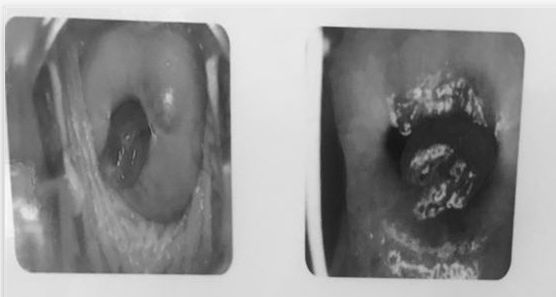

幽门螺杆菌感染的症状有哪些?

1、1口臭幽门螺杆菌是引起口臭的最直接病菌之一,由于幽门螺杆菌可以在牙菌斑中生存,在口腔内发生感染后,会直接产生有臭味的碳化物,引起口臭2胃肠疾病症状幽门螺杆菌感染的患者多会出现餐后嗳气恶心腹胀腹部不适的胃肠疾病症状...